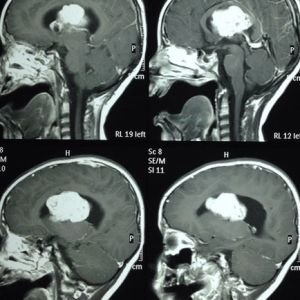

ESCLEROSIS TUBEROSA